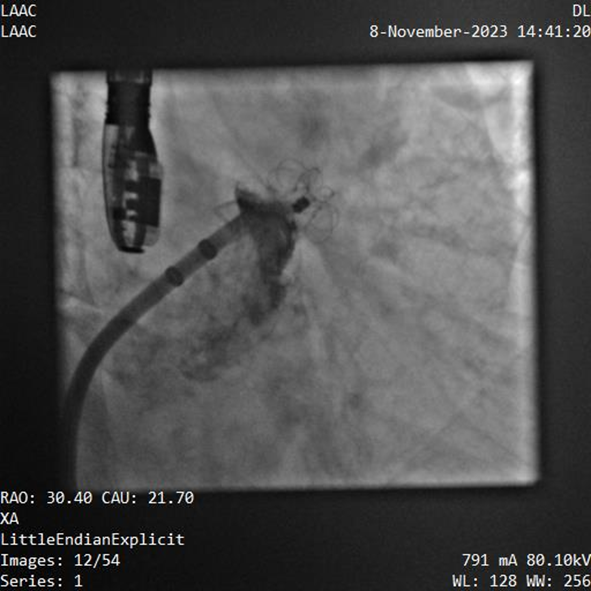

器械釋放后造影示封堵器展開良好,封堵完全

該例患者為男性58歲,陣發(fā)性房顫,9個月前突發(fā)急性腦梗死,3月前曾行房顫射頻消融術。2023年11月經(jīng)胸超聲心動圖示左房內(nèi)徑46mm,經(jīng)食道超聲心動圖示左心房及左心耳內(nèi)未見血栓形成,CHA2DS2-VASc評分3分,HAS-BLED評分2分。DSA測得左心耳開口直徑約23mm,錨定區(qū)域約18mm。

手術過程順利,通過植入非常規(guī)固配規(guī)格的固定部20mm、封堵盤28mm的左心耳封堵器,實現(xiàn)左心耳完全封堵,達到手術預期效果,再次體現(xiàn)產(chǎn)品獨特的設計創(chuàng)新優(yōu)勢。